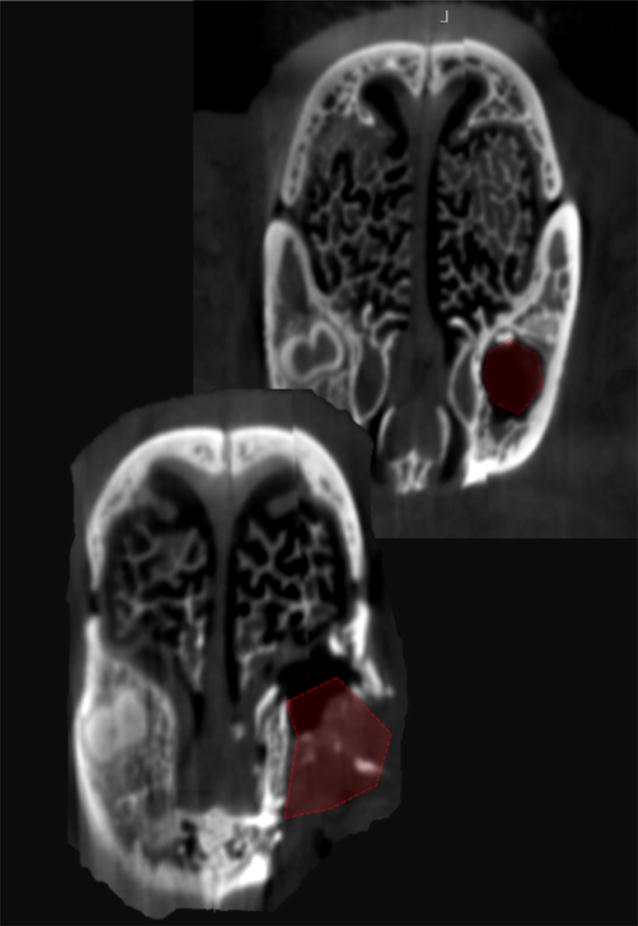

摘要:本研究的目的是在不损害动物的健康情况下建立一种适当模拟临床缺陷环境的组织工程骨替代材料的牙槽突裂动物模型。创裂手术的目的是创造一个完整的齿槽裂,宽的骨缺损,上皮衬里(口腔粘膜)覆盖在裂隙缺损上。方法:对死后新西兰兔的颅骨进行成像调查。一个微型计算机断层扫描影像预试验来证实手术的可行性和缺陷。对16只,8周龄的建立体内齿槽裂手术动物模型进行了测试和评价。结果:临床检查和影像学分析,在所有兔子模拟牙槽突裂手术后8周发现一个广泛的骨骼缺陷延伸到鼻粘膜。结论:我们的外科技术成功地创建一个相当大和可预测的骨移植材料试验模型。该模型允许模拟裂区环境,可用于评价各种骨移植材料在骨形成和愈合潜力方面的效果,而不损害动物的健康。关键词:动物试验 唇腭裂 移植法 组织工程 兔背景:先天性牙槽嵴裂是一种畸形,是由于在妊娠4~12周内未融合原腭引起的。牙槽突裂修复的目的是建立上颌骨牙槽嵴的骨连续性。密封口鼻传播,为口腔修复创造良好的解剖学。应用自体骨、同种异体骨和异种骨移植材料以及各种组织工程骨替代材料进行牙槽突裂植骨。优化现有骨移植材料的质量,寻找新的、更好的骨替代材料是提高临床疗效的关键。各种移植材料的实验测试需要预先建立一个适当的生物学模型来进行实验研究,并评估骨形成和愈合的临床效果。模拟牙槽突裂的动物模型被认为是适当的临床干预试验的实验模型。一些动物模型已被用于检测齿槽裂植骨材料包括小鼠,大鼠,兔,猫,狗,猪,山羊,绵羊和猴。在实验动物中的牙槽突裂的发展是可以实现的,无论是手术或先天所致宫内胚胎发育过程。与大的模型,包括兔子相比,啮齿类动物模型有其固有的局限性。啮齿类动物有较小的长骨,更脆弱的皮层,不在皮质显示骨型重构。兔子没有攻击性,容易观察,在妊娠和成熟方面时间较快。兔的骨组织学与人类骨不太相似。文献报道了兔和人骨密度和断裂韧性的相似性。与灵长类动物和啮齿类动物相比,兔子表现出快速的骨骼代谢和骨转换率,主要是皮质重塑。为了正确地模拟人的体内环境,兔模型是一种适合于牙槽嵴裂实验研究的动物模型。因为兔子是可重复的,精确的,易于内部处理,比较容易麻醉,提供足够大的面积进行测试和可以承受手术创伤大小适当的哺乳动物。方法:微焦点CT(微CT)成像调查:通过对兔颅骨的显微CT成像,获得了骨骼解剖的影像学分析,以评估牙槽突裂的可行性和裂裂手术的计划。使用横断面切片和三维重建进行图像评价。先天性牙槽嵴裂手术与微CT成像:对已死亡的家兔头部进行了外科手术。不需要经过动物伦理委员会的批准,因为这一程序是在一个被处死的动物上进行的,而这只动物曾被用于另一个动物试验项目。根据所提出的程序进行裂裂手术。术后微焦点CT(Micro-CT)评估兔颅骨缺损。体内牙槽突裂形成术:动物、麻醉和饲养 实验手术前30 min 用盐酸甲苯噻嗪5mg/kg,肌肉注射麻醉家兔. 兽医按照已经使用的方法对动物进行镇静、麻醉和护理。研究期间动物单笼饲养,动物按照统一协议饲养观察直到试验结束。新西兰兔体内牙槽突裂手术(n = 16)上颌牙槽突手术部位的准备:兔仰卧位手术在无菌条件下进行。在左侧中切牙外侧进行2厘米左右的线性粘膜切口。沿着牙弯曲,延伸到左中切牙的远中颊角,然后延伸到中线乳头面部左侧中央切口的牙龈边缘。拨开牙龈和软组织暴露上颌牙槽和中切牙牙周附着。随后,皮瓣骨膜下暴露鼻孔。用弯曲的骨膜剥离器保护和提高鼻粘膜不要刺破鼻粘膜。用一个圆形硬质合金牙钻的旋转器械,在左侧中切牙的外侧弯曲处进行侧截骨,以形成一个显露中切牙根的窗口。用小牙挺将中央切牙轻轻脱位向侧壁,后使用兽医拔牙钳提取。进一步的截骨手术去除上下用咬骨钳骨板暴露鼻粘膜不损伤粘膜。然后将骨蜡应用于缺损的骨壁,并近似口腔粘膜。在内侧和外侧用可吸收缝线缝合。伤口中央部分开着,形成一个口袋,可以俯视骨缺损。最后用氧化纤维素填充缺陷。整个手术过程中鼻粘膜保持完整。动物被允许8周的时间来修复缺损和形成上颌牙槽缺损。第二阶段采用相同的手术准备和严格的手术,暴露牙槽骨缺损进行骨移植。牙槽骨缺损部位作一个近缘切口分离口腔。暴露骨缺损,用牙钻固定骨壁。家兔术后直接喂饲软饲料。手术后牙槽突裂的锥形束CT:在造模术后8周,用锥形束CT对兔颅骨进行了术后成像。结果:新西兰白兔颅骨骨调查:新西兰兔上颌前牙的窝藏两配对中切牙和双附件腭侧切牙。中切牙突出,呈半圆形,副腭切牙较小,约占中切牙长度的一半。取出一根中切牙检查颅骨,发现突出的牙齿穿过鼻孔下方的上颌骨,留下一层薄薄的骨,将牙槽窝与鼻粘膜分开。取出的中切牙牙槽窝形成7~8毫米的囊状腔,是牙槽裂研究的理想模型。一旦上下骨板被切除,以产生一个连续的缺陷,模拟常见的先天性齿槽裂患者。先天性牙槽嵴裂手术与微CT成像:兔颅骨牙槽突裂手术的模拟研究显示创建一个适当大小的缺损的可行性。这种缺陷可以很容易地扩展到鼻粘膜来模拟真实的临床缺陷。很容易封闭软组织和缝合黏膜。缺损的三维显示一个宽度为8毫米的三角形牙槽裂缺损。模拟牙槽裂缺损患者的临床表现。新西兰兔体内创造手术牙槽突裂:每只兔的手术时间在15到30分钟之间,所有的程序都可以在没有气管插管的氯胺酮麻醉期间进行。在少数情况下需要额外注射氯胺酮。出血是轻微的,这些动物在手术后立即活跃并表现得很好。动物在手术后的第一天就开始进食了。动物在整个研究期间自由采食。所有兔术后8周存活,直至处死。术后牙槽突裂CT:在8周的愈合后,在一个动物身上进行了计算机断层扫描。缺损部位的三维图显示一个宽度为8毫米的三角形牙槽裂缺损。延伸到与缺陷部位尖鼻并对牙槽窝的深度进行了验证。结论:一种简单、可预测的牙槽突裂兔模型的临床试验。组织工程骨替代材料可以根据现有的解剖结构建立。中切牙的拔牙术,通过将其延长到鼻粘膜来修改拔牙窝,在腭裂修复期的应用简易骨蜡和氧化纤维素材料避免骨的快速生成和缺损的填充。允许8周的愈合产生一个可预测的大小缺陷,可用于以后的移植过程。